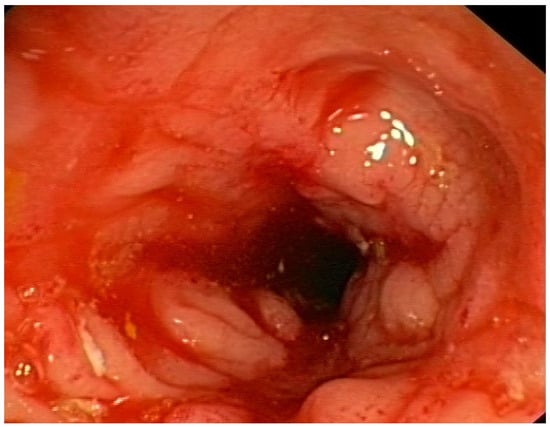

Figure 6.

Inflammation, swelling and narrowing of the intestinal lumen in a patient with Crohn’s disease.